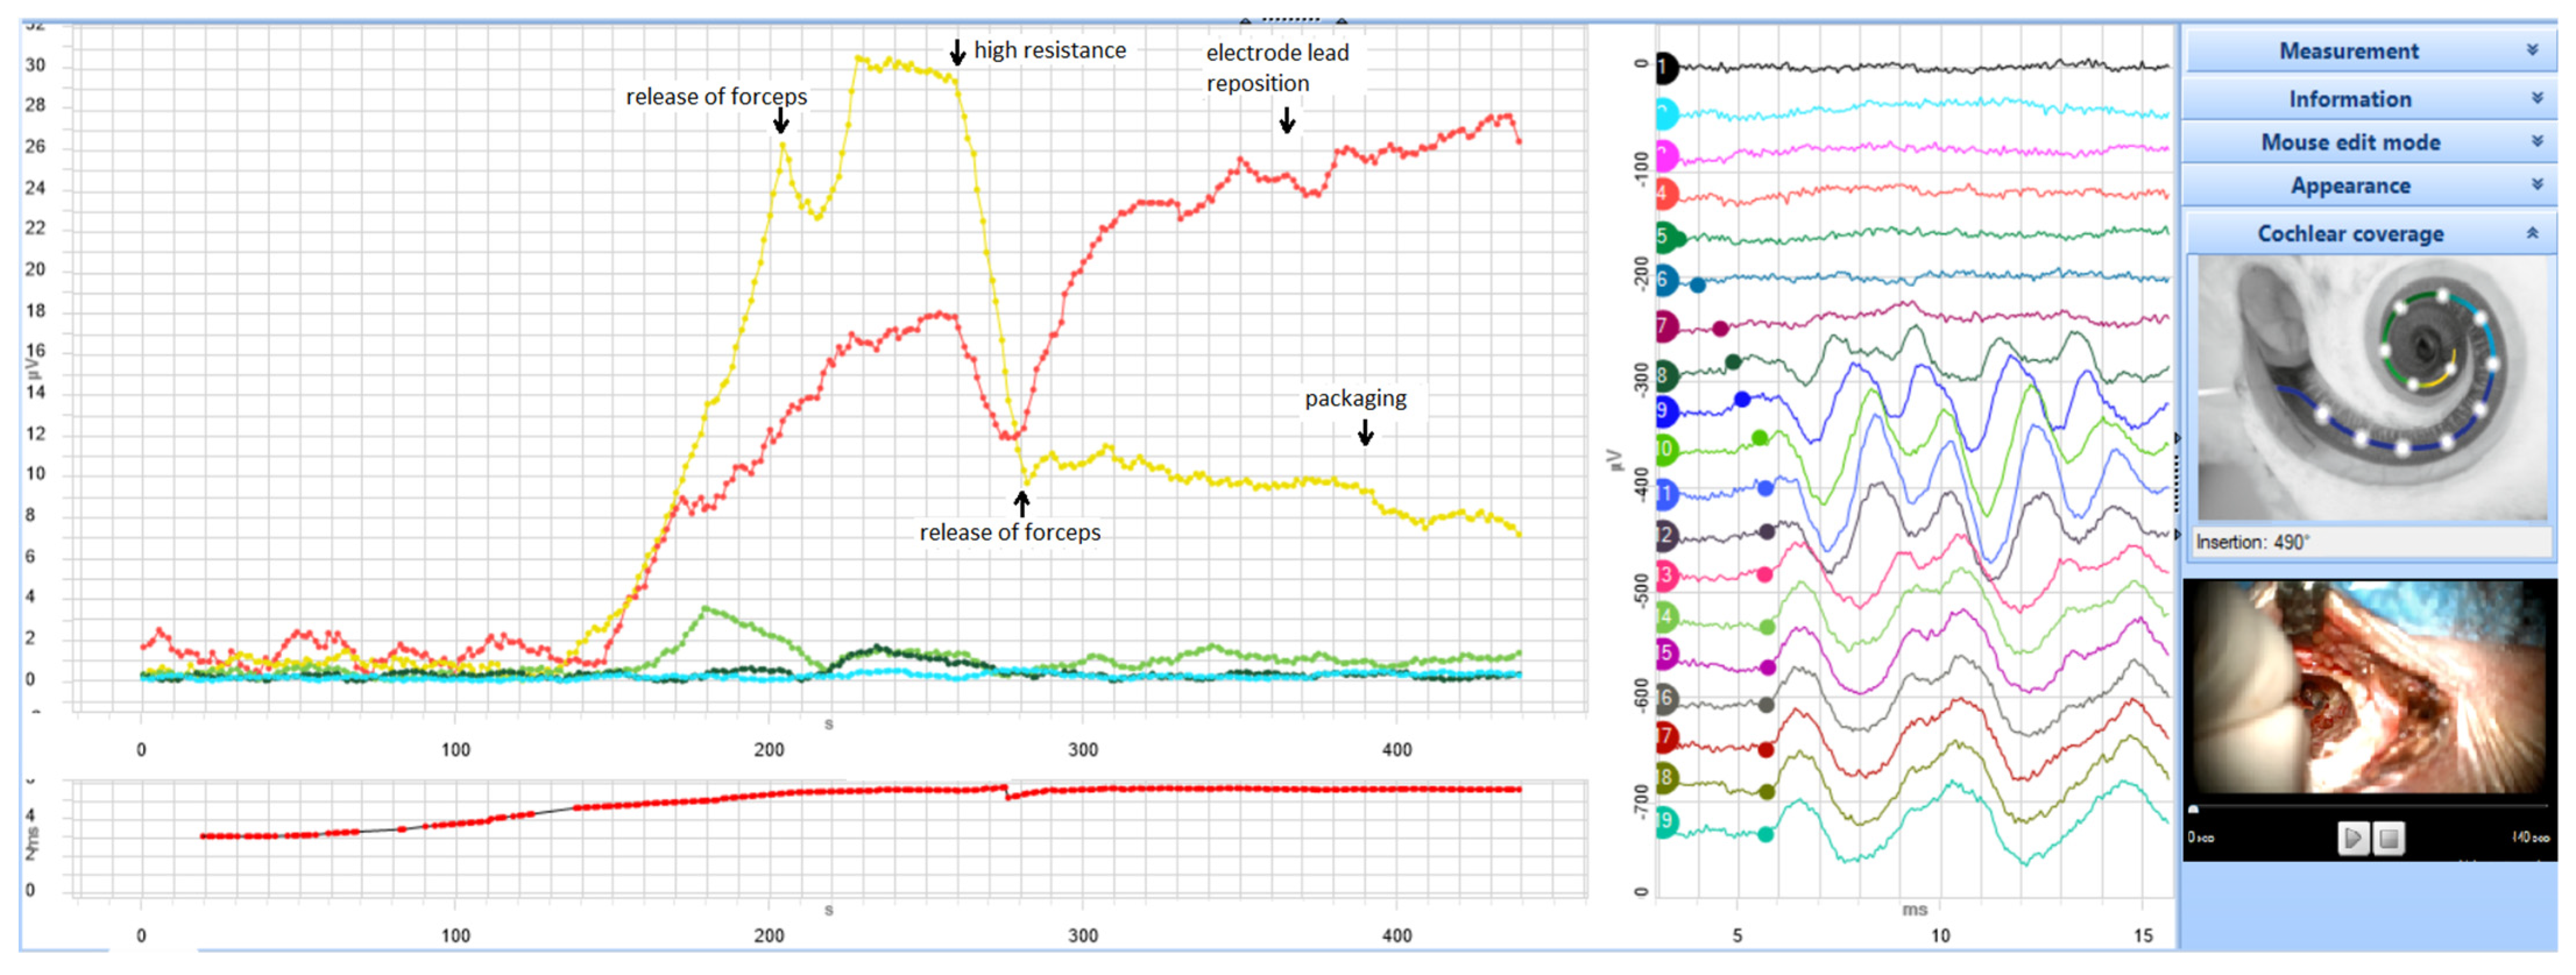

経食道心エコー法マニュアル 改訂第3版 | 渡橋 和政 |本 | 通販。経食道心エコー法マニュアル[Web動画付](改訂第5版) | 渡橋 和政。経食道心エコー法マニュアル 改訂第4版 | 渡橋 和政 |本 | 通販。淡路島。TRAF7-targeted HOXA5 acts as a tumor suppressor in prostate。Tracoe Cuff Pressure Monitor Sensitive - Atos Medical。First-in-human Results of the Novel Transcatheter Mitral。製品詳細 | 村中医療器 情報サイト | 経食道用 エコープローブ。Multi-Frequency Intraoperative Monitoring of Hearing。心エコー法 | 2020年版 心アミロイドーシス診療ガイドライン。房室弁の心エコーによる解剖学的評価。「経食道心エコー法マニュアル = Practical Manual of Transesophageal Echocardiography」渡橋 和政定価: ¥ 15000#渡橋和政 #渡橋_和政 #本 #自然/医療・薬学・健康裁断済みです。9784524258956.jpg。表紙に寄れがありますがそれでもよければどうぞ2024年9月末で出品終了します。周術期経食道心エコ-図: 効率的に学ぶために | ロジャ-・L。